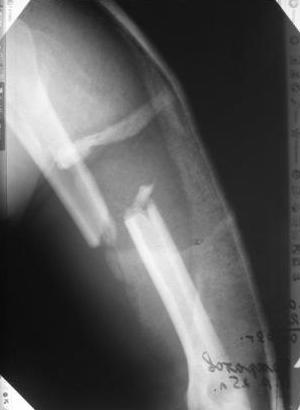

Re: Перелом н\3 плечевой кости. Тактика лечения?

Да, как раз блокированная пластина и стоит, не синтезовская метадиафизарная, Рыбинская, но на порядок дешевле, а профилактика всех осложнений - в данном конкретном случае, начало ранней на вторые сутки - после удаления дренажа разработки движений в смежных суставах. Если же идти с ревизией т.е. всё равно, открыто как вариант небольших разрезов при поперечном переломе можно и комбинированный мос (см.на вкладыше), хотя думаю для такого способа перелом всётаки низковат.